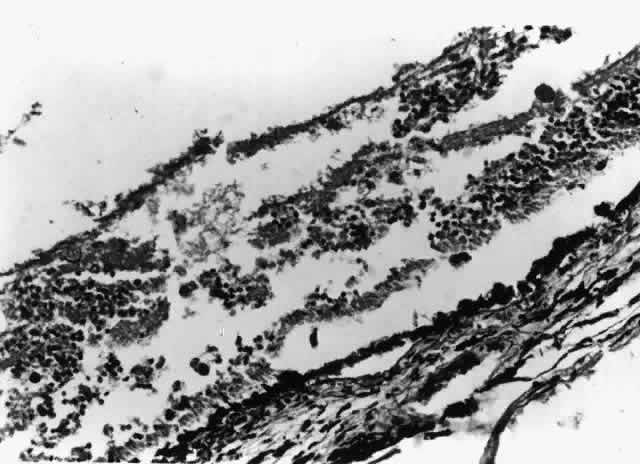

Histologic studies of AIDS-related CMV retinopathy demonstrate the tissue necrosis and cytomegalic cells characteristic of all CMV infections (Fig. 1).9,17 Electron-microscopic and immunochemical studies have identified CMV viral particles and antigen in a patchy distribution throughout all layers of the retina and occasionally in contiguous retinal pigment epithelial cells.9 Viral antigens are only rarely identified in the choroid.9,18 Viral antigen in the choroid has been found in association with vessels and is not always adjacent to areas of retinopathy, suggesting that the virus reaches the choroid through independent hematogenous spread rather than by extension of infection from the retina.

Fig. 1. CMV retinopathy, with neutrophilic infiltration in an area of necrotic retina. Cytomegalic cells with intranuclear inclusions are present in the center of the field (hematoxylin-eosin; original magnification × 600). (Printed with permission from Pepose JS, Holland GN, Nestor MS et al: Acquired immune deficiency syndrome: Pathogenic mechanisms of ocular disease. Ophthalmology 92:472, 1985)

Among cases of AIDS examined at autopsy, 22% to 50% of those with CMV retinopathy have neutrophilic infiltrates in retinal tissue.9,19 This finding is atypical when compared with CMV retinopathy in non-AIDS patients, in which only a sparse lymphocytic infiltrate is observed. The difference has been attributed to intact granulocyte function and chemotaxis in patients with AIDS, in contrast to infants, organ transplant recipients, and patients with malignancies who can have more severe quantitative or qualitative granulocyte dysfunction.9 It has been noted that patients on immunosuppressive drugs can develop marked inflammatory reactions to CMV retinopathy when such drugs are withdrawn.14 Acute inflammatory cells may extend into the adjacent choroid despite the absence of identifiable viral antigens.9 The vitreous usually remains remarkably free of inflammatory material, despite the presence of virus in the vitreous cavity.20